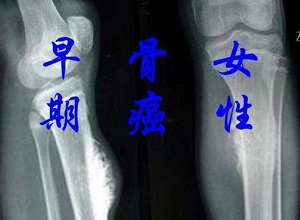

郑州肿瘤医馆排名:骨癌早期身体会有什么症状?骨癌是一种恶性骨肿瘤,其早期症状包括局部骨肿块.疼痛.功能障碍,如果肿瘤体积较大,可导致相应部位出现压迫症状。

1.局部骨肿块:即部分骨癌患者可接触局部固定肿块或局部肿胀,一常见的是关节肿胀,表现为关节附近红肿.发热等。

2.疼痛:是本病早期一重要的症状。疾病初期疼痛较轻,主要是局部间歇性疼痛,表现为刺痛.拉痛等,按压时疼痛加重。大多数患者在晚上.休息时疼痛比较明显,或者疼痛可以扩散到远处。

3.功能障碍:由于疼痛和肿胀,临近关节的肿瘤可引起关节活动障碍。